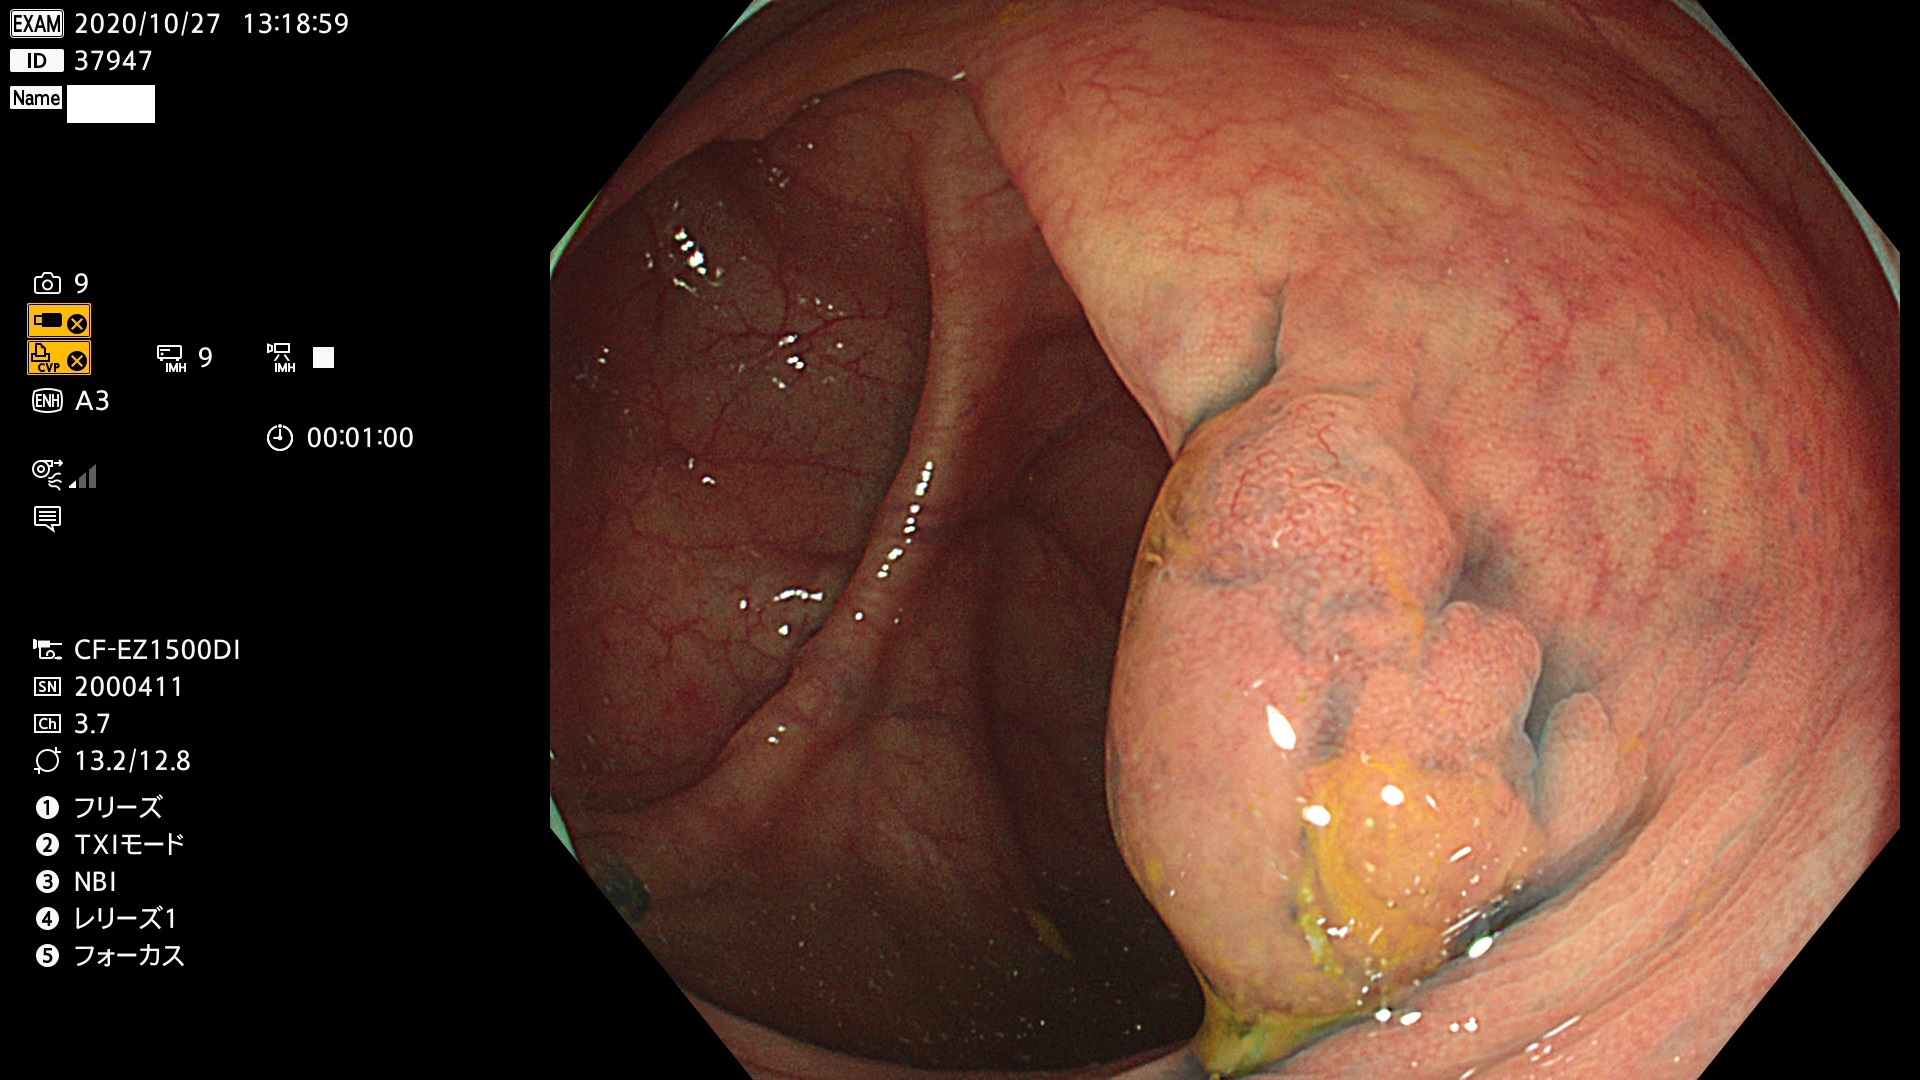

腺腫発見率 78  % (カルテ番号 37900〜37999の100名の方の検査結果で集計)

37900 37902 37903 37904 37905 37906 37907 37909 37910 37911 37912 37913 37914 37915 37916 37917 37919 37921 37922 37923 37926 37928 37929 37930 37931 37933 37934 37935 37936 37937 37938(SSAPのみ) 37939 37940 37941 37942 37943 37946 37947 37948 37949 37951 37952 37953(SSAPのみ) 37955 37956 37957(SSAPのみ) 37958(SSAPのみ) 37960 37962 37963 37964 37966 37967 37968 37971 37972 37973 37975 37976 37977 37979 37982 37983 37984 37985 37986 37987 37988 37989 37990 37991 37992 37993 37994 37995 37996 37998 37999

発見困難で危険性の高い平坦型病変(上記100名より抽出)